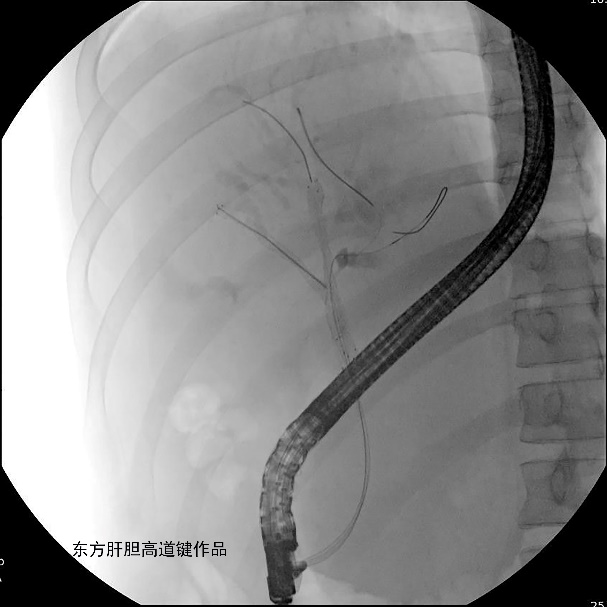

为解决胆道梗阻,于2022年3月1日行ERCP。

图A

图A:胆总管造影见胆总管未见异常,肝门胆管细线样狭窄,累及肝总管、分叉、右前、左内及左外肝内胆管,各胆管分支间通而不畅;